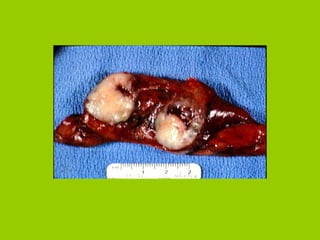

Normal Lung vs. Cancerous Lung

Normal Lung vs.Cancerous Lung

Types of LungCancer Bronchogenic carcinoma Most common Arise from bronchial epithelium Squamous cell carcinoma Develop from epithelial lining in bronchus Project into airway Adenocarcinomas and bronchoalveolar cell carcinoma Found on lung periphery Less symptomatic, more difficult to treat Small cell carcinoma Rapidly growing; located near major bronchus Invasive and metastize early in dev Large cell carcinoma Found in periphery Consist of large, undifferentiated cells Rapid growth rate, metastize early